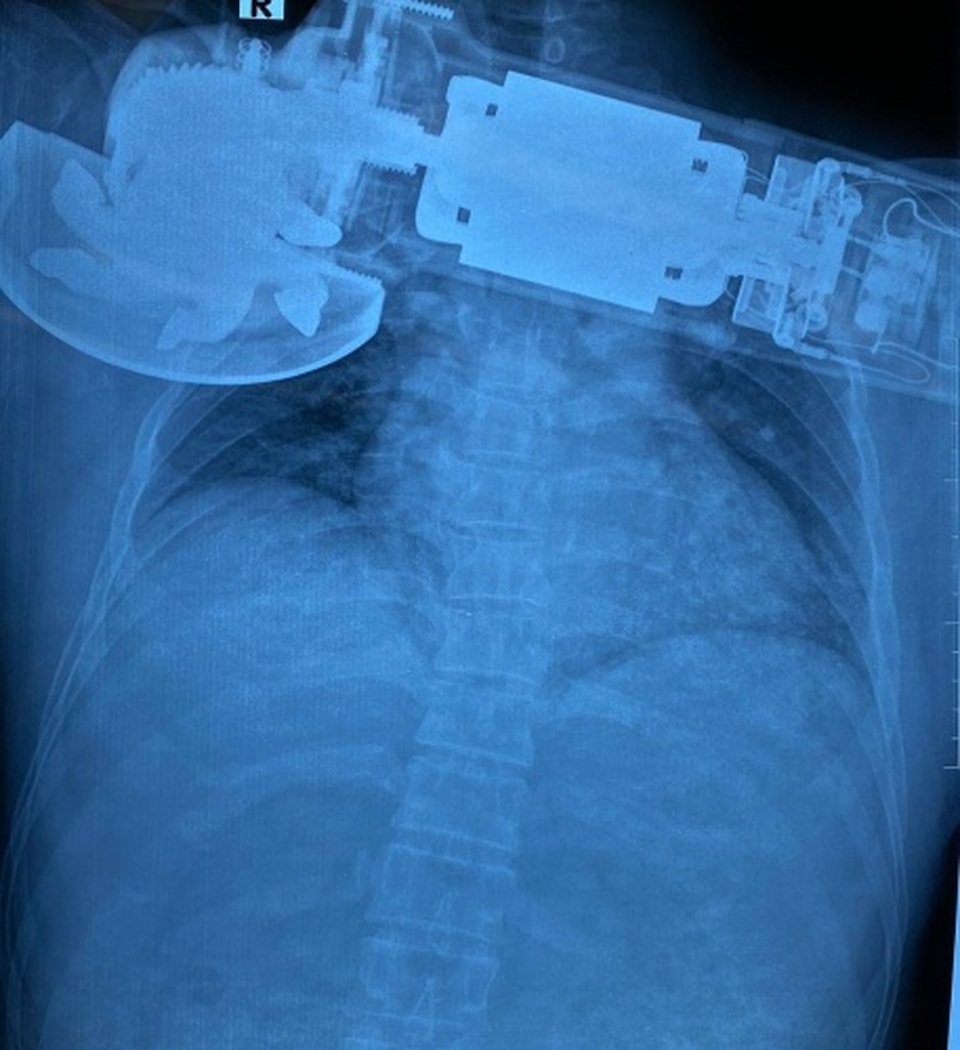

Bệnh viện Trung ương Quân đội 108 mới đây tiếp nhận một trường hợp ở Bắc Ninh bị máy chà văng, cắm găm vào ngực phải. Bệnh nhân được chỉ định mổ cấp cứu xử trí vết thương.

Theo bác sĩ Bệnh viện Trung ương Quân đội 108, bệnh nhân nhập viện trong tình trạng tỉnh, vết thương không chảy máu, không khó thở, huyết động ổn. Máy chà găm sâu vào thành ngực phải, sát bờ dưới xương, bờ mép vết thương nham nhở. Phần mềm thành ngực bị cuốn vào trong máy chà gây khuyết hổng phần mềm, mất da và bầm dập da quanh tổn thương.

Bác sĩ Lê Hải Sơn, Phó Chủ nhiệm khoa Ngoại lồng ngực, người trực tiếp tiến hành phẫu thuật cho biết bệnh nhân bị bong lóc phần mềm, mất da và bầm dập da rất lớn ở vùng ngực bên phải. Rất may, bệnh nhân chưa có tổn thương mạch máu, ở khoang màng phổi.

“Trong quá trình xử trí, chúng tôi thấy có tổn thương đứt bán phần của cơ ngực lớn, cơ ngực bé và cơ gian sườn hai. Các bác sĩ đã xử trí cắt lọc, khâu lại những tổn thương đứt rách của cơ ngực lớn, cơ ngực bé; rửa sạch vết mổ và khâu lại vết thương phần mềm”, BS Sơn nói.